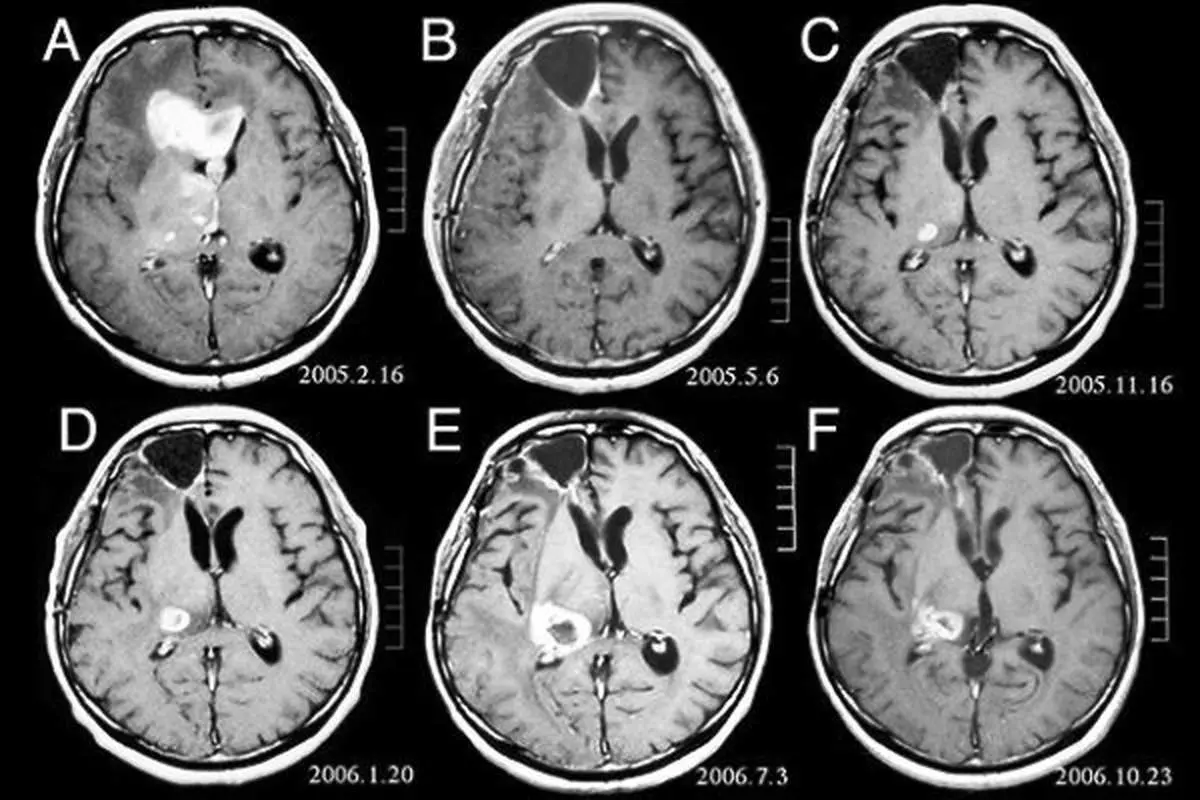

محققان کالج امپریال لندن عنوان می کنند این یافته ها می تواند شیوه استفاده از تصویربرداری مغز را به عنوان یک نشانگر زیستی برای اندازه گیری شرایط بیولوژیکی معرفی کند.

محققان اسکن مغز حدود ۷۰۰ فرد بزرگسال را در اسکاتلند که همگی در سال ۱۹۳۶ بدنیا آمده بودند بررسی کردند. مطالعات نشان داد کسانی که اسکن مغزشان از سن تقویمی شان پیرتر بود ضعیف تر بودند، عملکرد ریوی ضعیفی داشتند و سرعت راه رفتن شان آهسته تر بود.

همچنین افراد دارای مغز پیرتر، بسیار در حل مسائل جدید بد عمل می کردند و به هنگام بکارگیری الگوهای منطقی، عملکرد ضعیف تری داشتند.

محققان عنوان می کنند که تلفیق معیارهای سن بیولوژیکی به تعیین خطر مرگ ناشی از افزایش سن کمک خواهد کر